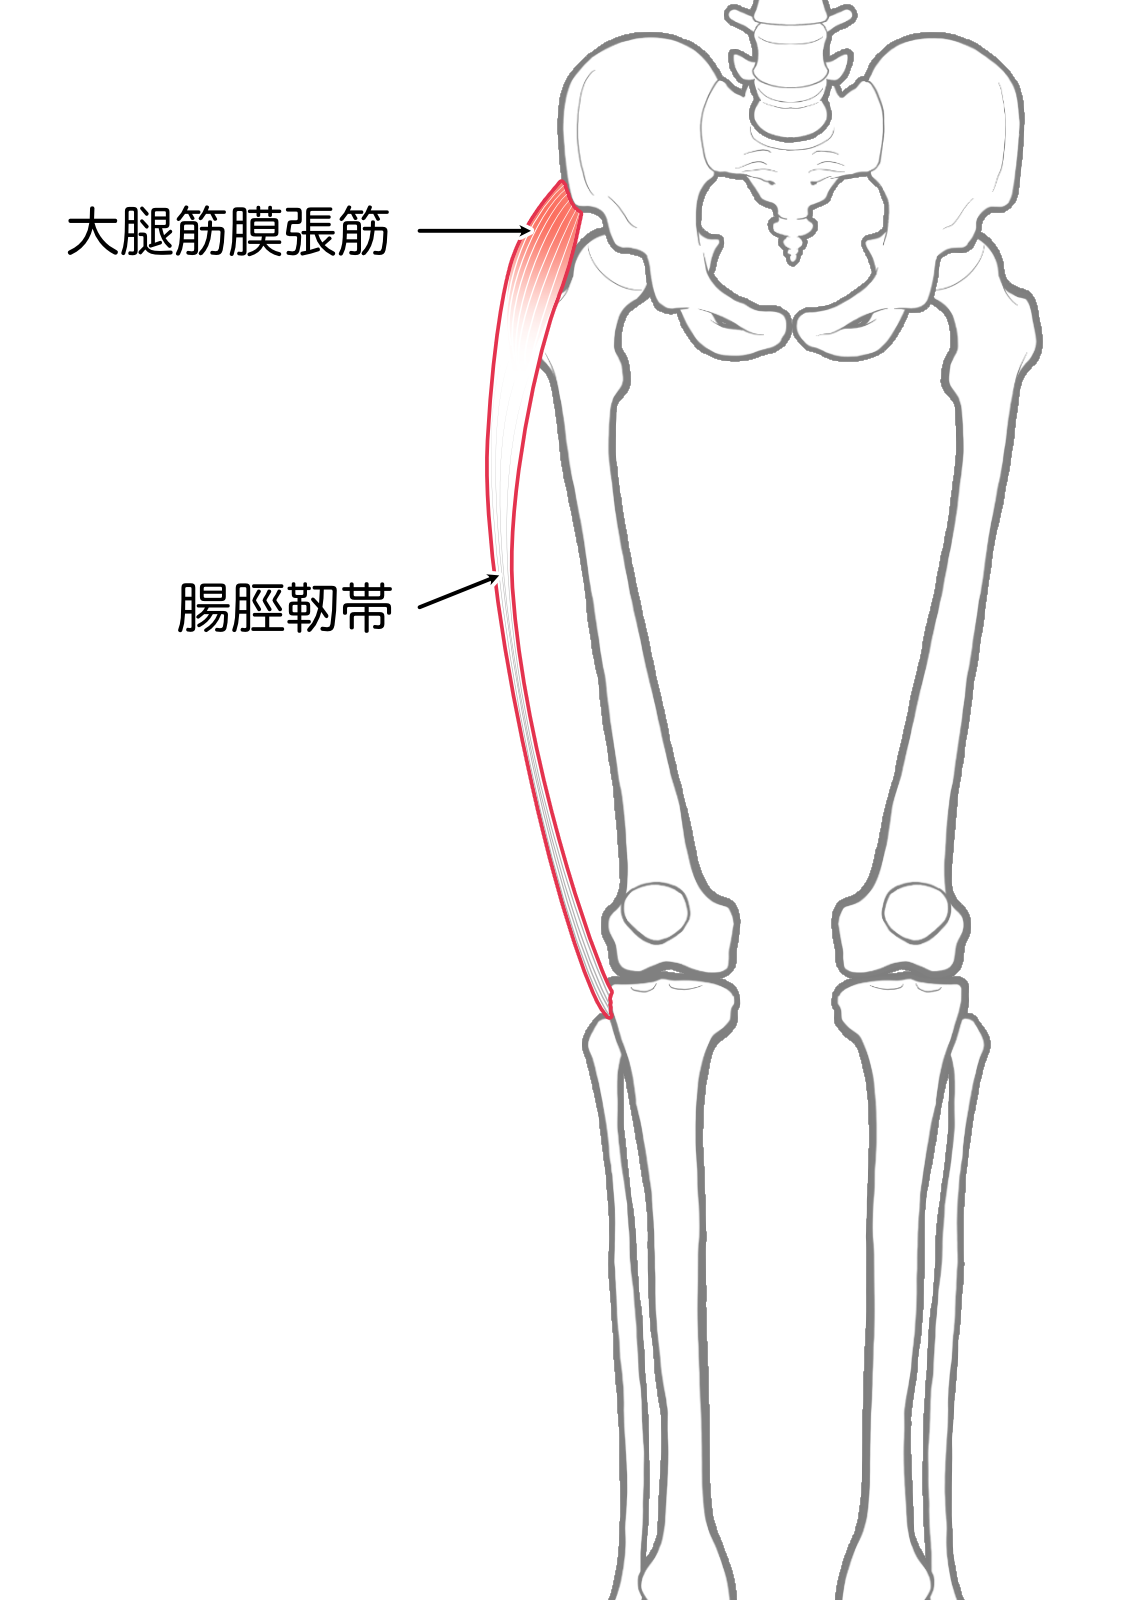

大腿筋膜張筋

| 起始 | 上前腸骨棘 |

| 停止 | 腸脛靭帯を経て 脛骨外側顆 |

| 神経 | 上殿神経L4-S1 |

| 作用 | 膝関節伸展(伸展位), 屈曲(屈曲位),外旋 |

- 大腿筋膜張筋(屈曲位)

- 大腿筋膜張筋(伸展位)

- 大腿筋膜張筋